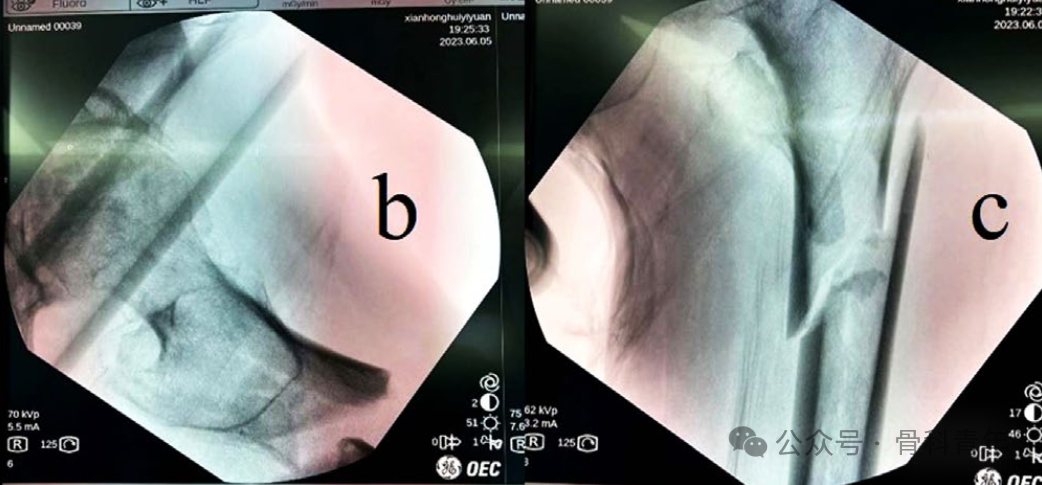

与传统的粗隆下骨折的牵引复位一致,先轴向牵引,后内旋内收复位,复位后可见近端骨折端屈曲外展移位:

在透视引导下,自骨折线上方1cm,股骨中线偏后1cm作小切口,将血管钳紧贴股骨前方骨皮质置入,并插入内侧肌肉中,后上提血管钳,将股骨近端往下按压,复位屈曲的股骨近端: